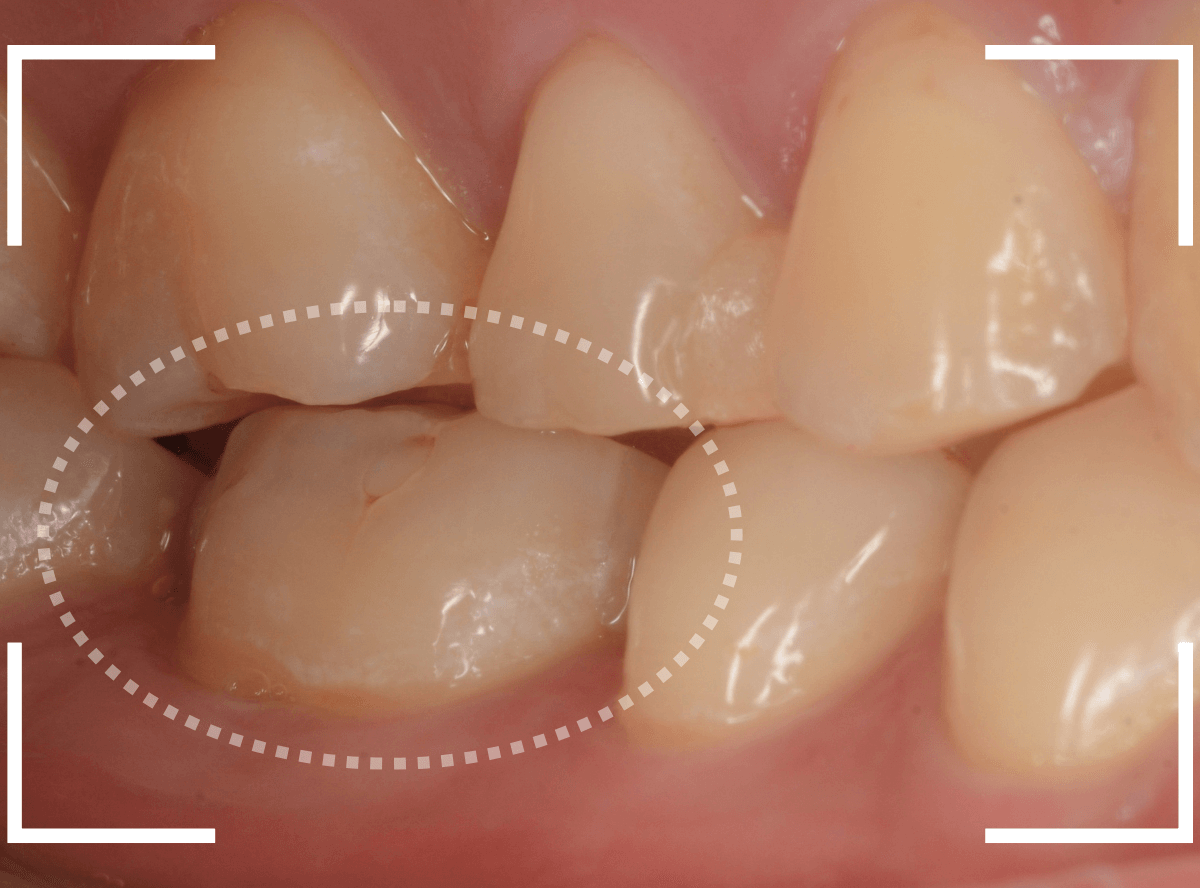

Case.29

舌のそばの虫歯とセラミック治療

下の奥歯が虫歯になった患者さんのケースです。

〇部が虫歯の部分です。

写真で見てわかるように、常に舌が歯に触っているような状況です。

このような場合、虫歯を見つけづらいですし、治療の難易度もあがります。